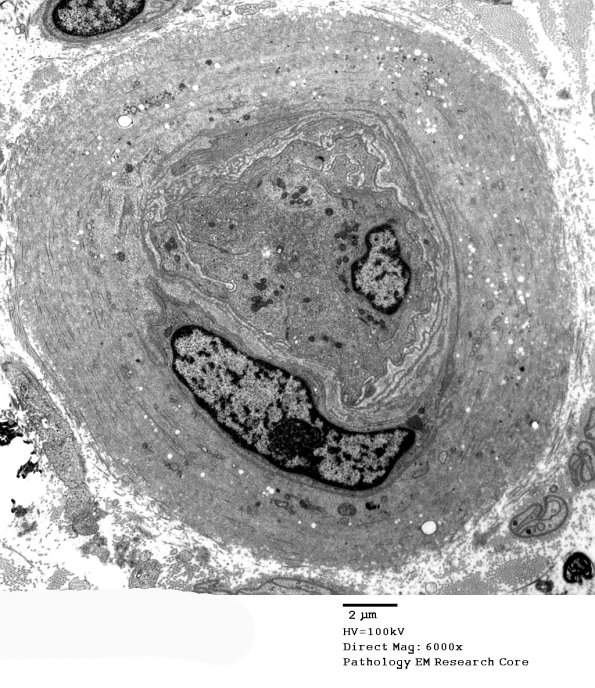

EM confirms the moderate loss of large and small myelinated axons and demonstrates the significant loss of unmyelinated axons. There is no demyelination. ---- 4B1-3 Ultrastructural evidence demonstrates a few turns of basement membrane surrounding vessels and preponderant collagen deposition. (electron micrographs)